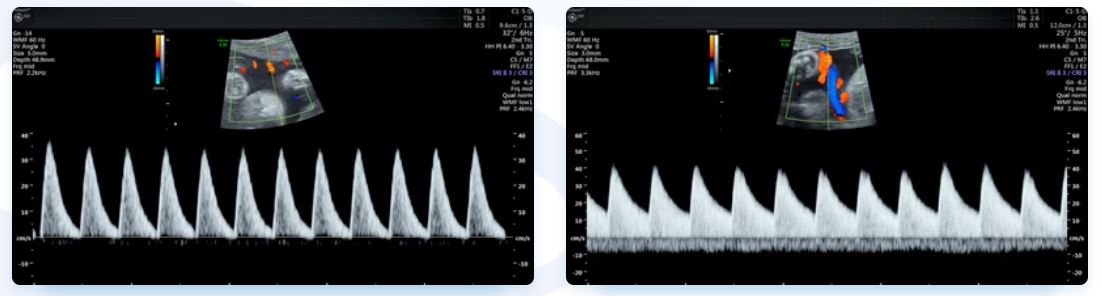

Currently, standard-of-care ultrasound scans measure blood flow at one point in the umbilical cord. The technique developed by Sled and his collaborators takes two measurements – one at the fetal end of the umbilical cord and one at the placental end. Sled says recording both measurements gives a much more accurate picture of the way blood is travelling through the umbilical cord.

First image: Ultrasound scan showing abnormal blood pulse pattern, indicating MVM.

Second image: Ultrasound scan showing normal blood pulse pattern.